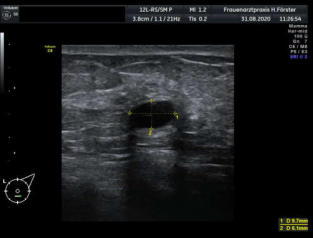

Gynäkologische Grundversorgung Frauenärztliche Krebsfrüherkennungsuntersuchung Nachsorge und supportive Therapie bei bösartigen gynäkologischen Tumoren Impfungen Brustultraschall Ultraschalluntersuchung der weiblichen Genitalorgane Psychosomatische Grundversorgung Chlamydienscreening FOB-Test (früher Hämoccult) Kontrazeption Geburtshilfliche Grundversorgung Geburtshilflicher Basisultraschall Erweiterter Basisultraschall (Organscreening) zw, 18-22.SSW Doppler/Duplexsonografie des fetomaternalen Gefäßsystems Infektionsscreening in der Schwangerschaft CTG (Kardiotokographie) Gynäkologische Grundversorgung Dies umfasst die Abklärung und Behandlung gynäkologischer Erkrankungen. Eine große Rolle dabei spielt das ärztliche Gespräch, ergänzt bei Notwendigkeit durch die gynäkologische Untersuchung oder Untersuchung der weiblichen Brust. In vielen Fällen werden noch Zusatzuntersuchungen durchgeführt (z.B. Ultraschalluntersuchungen, Abstrichentnahmen, Blutentnahmen) oder weiterführende Untersuchungen veranlasst (z.B. Röntgenuntersuchungen). >> zurück << Frauenärztliche Krebsfrüherkennungsuntersuchung Die Krebsfrüherkennungsuntersuchung der Frau ist wahrscheinlich die bekannteste Leistung unseres Fachgebietes. Ab dem Alter von 20Jahren hat jede Frau ein Anrecht auf diese jährliche Untersuchung. Dabei werden der Unterleib der Frau und ab dem Alter von 30Jahren auch die Brüste der Frau systematisch klinisch untersucht. Zusätzlich erfolgte seit vielen Jahren ein Pap-Abstrich vom Gebärmutterhals. So konnten Zellveränderungen meist rechtzeitig erkannt und behandelt werden und es wurde erreicht, daß das früher sehr häufige Zervixkarzinom (Gebärmutterhalskrebs) heute nur noch selten auftritt. Um die Qualität weiter zu verbessern erfolgte 2020 eine Neuordnung des Screenings mit Überarbeitung der Abstrichintervalle und Hinzunahme von HPV-Abstrichen ab 35 als Kassenleistung. >> zurück << Nachsorge und supportive Therapie bei bösartigen gynäkologischen Tumoren Nach Abschluss und oft auch wärend der Primärbehandlung können Probleme auftreten. Es macht also Sinn, sich in regelmäßigen Abständen zu treffen, um das weitere Vorgehen zu planen, eventuell Zusatzuntersuchungen zu veranlassen oder zusätzlich wegen der Beschwerden zu behandeln. Die Nachsorgeuntersuchungen finden anfangs engmaschig statt, später werden die Intervalle länger. >> zurück << Impfungen In Zeiten der Globalisierung, zunehmender Reisefreudigkeit und Zuwanderung werden wir wieder mit Infektionserregern konfrontiert, die wir schon als besiegt geglaubt hatten. Gleichzeitig werden wir immer älter und unser Immunsystem dabei nicht besser. Es reicht nicht, mal eben alle 10Jahre Tetanus zu impfen. Sind Sie geschützt? Wissen Sie was empfohlen ist? Bringen Sie den Impfausweis (auch den alten!!) mit. Wir prüfen Ihren Impfstatus, geben Ihnen Empfehlungen. Die gängigsten Impfstoffe haben wir auch vorrätig und können Sie impfen. >> zurück << Brustultraschall Die Ultraschalluntersuchung der Brust (Mammasonografie) kommt zur Abklärung von krankhaften Veränderungen zur Anwendung oder als Zusatzuntersuchung in der Früherkennung von Brustkrebs bei sehr dichtem Gewebe oder familiärer Vorbelastung. Sie ersetzt nicht das organisierte Mammographiescreening und ist nicht Bestandteil der normalen Krebsfrüherkennung. Es handelt sich um eine schmerzfreie Untersuchung ohne Strahlenbelastung. Die Mammasonografie  ist auch als Wunschleistung (IGeL) möglich. >> zurück << Ultraschalluntersuchung der weiblichen Genitalorgane Die Ultraschalluntersuchung der weiblichen Genitalorgane kommt zur Abklärung von krankhaften Veränderungen des weiblichen Genitales zur Anwendung. Dabei werden mit einer hochfrequenten Vaginalsonde die Organstrukturen im kleinen Becken untersucht. Die Untersuchung ist bei schlanken und sehr jungen Frauen auch vom Bauch aus möglich, die Genauigkeit ist dabei technisch bedingt aber schlechter.  Sie ist nicht Bestandteil der normalen Krebsfrüherkennung. Auch diese Untersuchung ist als Wunschleistung (IGeL) möglich. >> zurück << Psychosomatische Grundversorgung Jede Erkrankung belastet die Seele. Eine seelische Belastung macht den Körper krank. Jeder weiß das. Die Zusammenhänge zwischen dem kranken Körper und der kranken Seele beschreibt die Psychosomatik. Ein "Gordischer Knoten", der nur schwer zu zerschlagen ist, oft ein langer Weg. Ziel ist es, diese Zusammenhänge zu erkennen und den Betroffenen zu helfen ihren Weg zu finden. Oft ist die Zusammenarbeit mit einer Psychologin/ Psychologen nötig. Wichtig ist die Hilfe bei den ersten Schritten. Laufen müssen Sie selbst. >> zurück << Chlamydienscreening Das Bakterium Chlamydia trachomatis kann beim Sex übertragen werden und zu Entzündungen und sogar zur Unfruchtbarkeit führen. Deshalb bezahlen die Krankenkassen bis zum vollendeten 25.Lebensjahr allen sexuell aktiven Frauen einen Suchtest auf Chlamydien. Sie müssen lediglich eine Urinprobe abgeben. Auch in jeder Schwangerschaft wird nach Chlamydien gefahndet. Da Frauen im Normalfall auch im Alter über 25Jahren sexuell aktiv sind und noch schwanger werden wollen bieten wir die Testung auch als Wunschleistung (IGeL) an. Der Test wird dann aus einem Abstrich aus dem Muttermund entnommen, dies kann bei der Krebsfrüherkennung mit gemacht werden. >> zurück << FOB-Test (früher Hämoccult) Im Alter von 50 bis 54Jahren bezahlen die Krankenkassen allen versicherten Frauen einen Stuhltest zur Früherkennung von Darmkrebs oder seiner Vorstufen. Mit 55Jahren können Sie sich entscheiden zwischen zwei Darmspiegelungen im Abstand von 10Jahren oder der Fortführung der Stuhlteste alle 2Jahre. Natürlich kann man Stuhlteste auch zwischen den Darmspiegelungen machen lassen oder auch bei Frauen jünger als 50. Wir bieten dies als Wunschleistung (IGeL) unseren Patienten an. >> zurück << Kontrazeption Ein selbstbestimmtes Leben als Frau ist bei uns in Deutschland eine Selbstverständigkeit. Das war nicht immer so.  Kinder-Küche-Kirche hieß es früher, damals, in der guten alten Zeit. Das ist zum Glück vorbei. Und begonnen hat alles mit der Pille. Frauen konnten endlich über ihren Körper selbst bestimmen, ohne Angst ihre Liebe leben.  Aber die Pille ist nicht alles. Viele Märchen sind im Umlauf, Fehlinformation. Aber auch fehlendes Wissen zu Risiken.  Wir beraten Sie gern. >> zurück << Geburtshilfliche Grundversorgung In der Schwangerenberatung werden die werdenden Muttis gemäß den geltenden Mutterschaftsrichtlinien vom Anfang der Schwangerschaft bis zur Abschlussuntersuchung (6-8 Wochen nach der Geburt) betreut. >> zurück << Geburtshilflicher Basisultraschall Nach Vorgabe der Mutterschaftsrichtlinie sind sind in der Schwangerschaft 3 Ultraschalluntersuchungen vorgesehen. Diese finden in der 8.-12. SWW, in der 18,- 22. SSW und in der 28.-32.SSW statt. Dabei werden der Zustand des Embryos/ Feten, des Fruchtwassers und der Plazenta beurteilt. >> zurück << Erweiterter Basisultraschall (Organscreening) zw. 18-22.SSW Bei der zweiten Ultraschalluntersuchung (zw.18.-22. SSW) erfolgt ein erweitertes Screening mit Beurteilung der Organstrukturen des Kindes. Diese Untersuchung ist Kassenleistung, kann aber bei Wunsch auch Abgewählt werden, dann wird nur der Basisultraschall durchgeführt. >> zurück << Doppler/Duplexsonografie des fetomaternalen Gefäßsystems Bei Aüffälligkeiten im Schwangerschaftsverlauf oder auch bei bestimmten Vorerkrankungen oder Erkrankungen in einer früheren Schwangerschaft kann es notwendig sein die Durchblutung des Mutterkuchens und der Gefäße des Kindes zu Untersuchen. Hier kommt das Dopplerverfahren als Erweiterung des normalen geburtshilflichen Ultraschalls zum Einsatz. Dies erlaubt eine schnelle Zustandsbeurteilung des Kindes pepaart mit einer zeitlich begrenzten Vorhersage über die weitere wahrscheinliche Entwicklung. Bei entsprechender Indikation ist diese Untersuchung als Kassenleistung abrechenbar. >> zurück << Infektionsscreening in der Schwangerschaft Die Suche nach Krankheitserregern im Krankheitsfall ist Kassenleistung. Routinemäßig prüfen wir Ihren Schutz vor Röteln und Windpocken , in jeder Schwangerschaft erfolgt ein Test auf Chlamydien. Zusätzlich empfehlen wir jeder Schwangeren einen Test auf eine Besiedelung mit Gruppe-B-Streptokokken vor der Geburt. Diese Streptokokken können zu schweren Atemwegsinfektionen des Neugeborenen führen. Eine vorbeugende Behandlung bei positivem Test kann dann unter der Geburt erfolgen. Bei Wunsch kann auch ein erweitertes Erregerscreening über unser Labor erfolgen (Wunschleistung). Eine wichtige Rolle spielt auch die Kontrolle auf einen Schutz gegen eine Toxoplasmoseinfektion. Bei fehlendem Schutz empfielt sich die regelmäßige Testung aus dem Blut auf eine frische Infektion. Auch dies ist eine Privatleistung, wird aber von den meisten Kassen erstattet. Eine nicht erkannte und somit nicht behandelte Erstinfektion in der Schwangerschaft kann zu schweren Schäden beim Kind führen. >> zurück << CTG Ab etwa der 30.Schwangerschaftswoche können wir bei Notwendigkeit im Ramen der Schwangerschaftsvorsorge die kindlichen Herztöne (Kardiographie) und simultan dazu die die Spannung der mütterlichen Bauchdecke (Wehenschreiber, Tokographie) graphisch darstellen. Das nennt man zusammen Kardiotokographie oder kurz einfach CTG. Die Auswertung des CTG‘s erfolgt nach dem Fisher-Score (Punkte-System) sowie nach qualitativen Kriterien und erlaubt uns eine gute Zustandsbeurteilung des Kindes in den späteren Schwangerschaftswochen. >> zurück <<